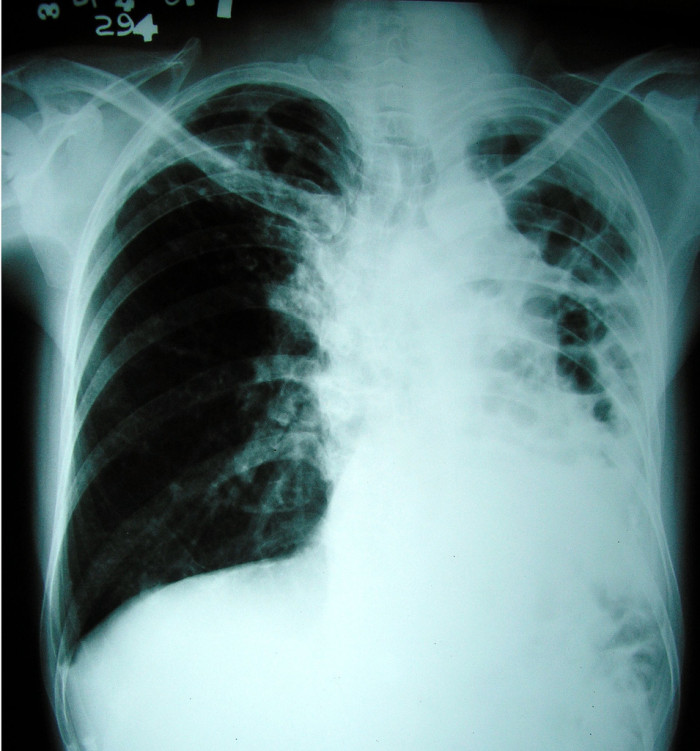

Home Cough dysfunction in the management of patients with dysphagia lungs

Dysphagia-Cough Dysfunction